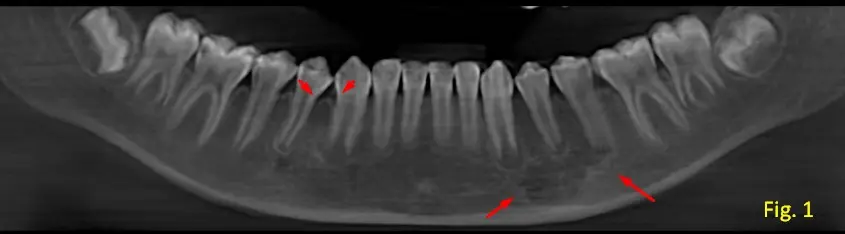

Se observa lesión hipodensa multilocular en la región del cuerpo mandibular izquierdo (sector de premolares), con una apariencia de vidrio esmerilado, correspondiente a la zona premolar-molar, con márgenes bien definidos y corticalizados (ver figura 1).

Presenta una tabla ósea en zona de pd 33,34,35 con abombamiento y en alguna zonas muy adelgazada, con posible ausencia de la misma (ver figura 2, vista axial).